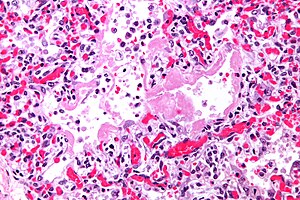

- Proliferative:

- Interstitial thickening.

- Inflammation (lymphocytes).

- Hobnailing of alveolar lining cells (type 2 pneumocyte hyperplasia[8]).

- Edema (link pink crap in the alveoli).

- Masson bodies in the airway.

- Hyaline material (usu. focal) - key feature.

- Proliferative phase DAD - intermed. mag. (flickr.com/Yale Rosen).

- Proliferative phase DAD - high mag. (flickr.com/Yale Rosen).